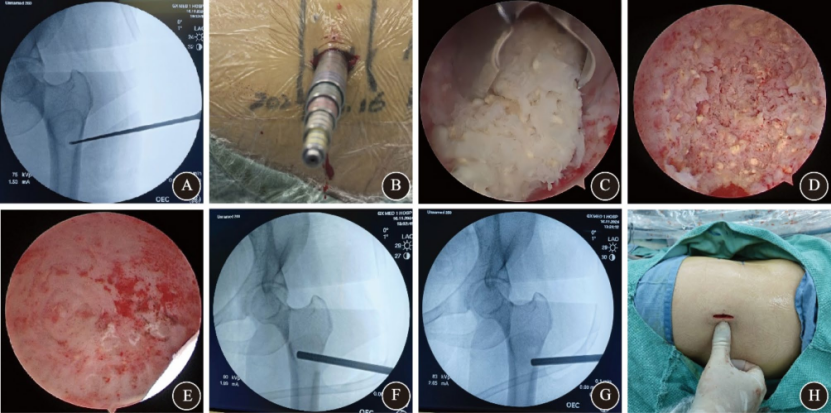

女性,49岁,检查发现发现左股骨近端占位性病变。患者无自觉症状,影像学显示左股骨近端椭圆形溶骨性病变,边界清晰,呈“磨玻璃样”改变,无皮质破坏或软组织侵犯。术前MRI提示囊性肿瘤样病变。初步诊断为良性骨肿瘤样病变。入院后广西医科大学第一附属医院脊柱骨病外科团队结合患者具体情况,制定个性化治疗方案。行AUNES辅助下肿瘤刮除+同种异体骨移植融合术。手术取左大腿近端外侧纵切口约1.5cm,透视引导下定位,逐步扩张通道,内窥镜下使用射频电极清理病灶周围组织,高速磨钻开骨窗,彻底刮除病灶后植入同种异体骨,术后病理提示骨纤维结构不良。术后第一天手术区轻度疼痛(VAS 3分),第三天出院。术后CT显示病灶腔完全被植骨填充,骨窗与肿瘤横径匹配良好。一个月随访时疼痛消失,切口愈合良好;三个月CT显示植骨融合进一步改善,无并发症发生。

图2 骨纤维结构不良患者术中影像